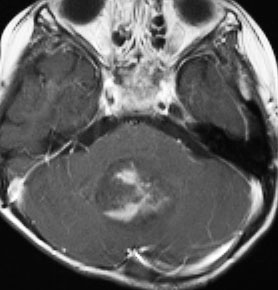

7歳児の小脳半球にある標準リスクの髄芽腫です。画像を一見すればこの髄芽腫は治るであろうと予測します。

手術で完全摘出し,退形成性髄芽腫の病理診断で,脳脊髄照射と局所照射54グレイ,シスプラチンベースの化学療法を6コース加えましたが,半年後に激しい播種再発を生じました。